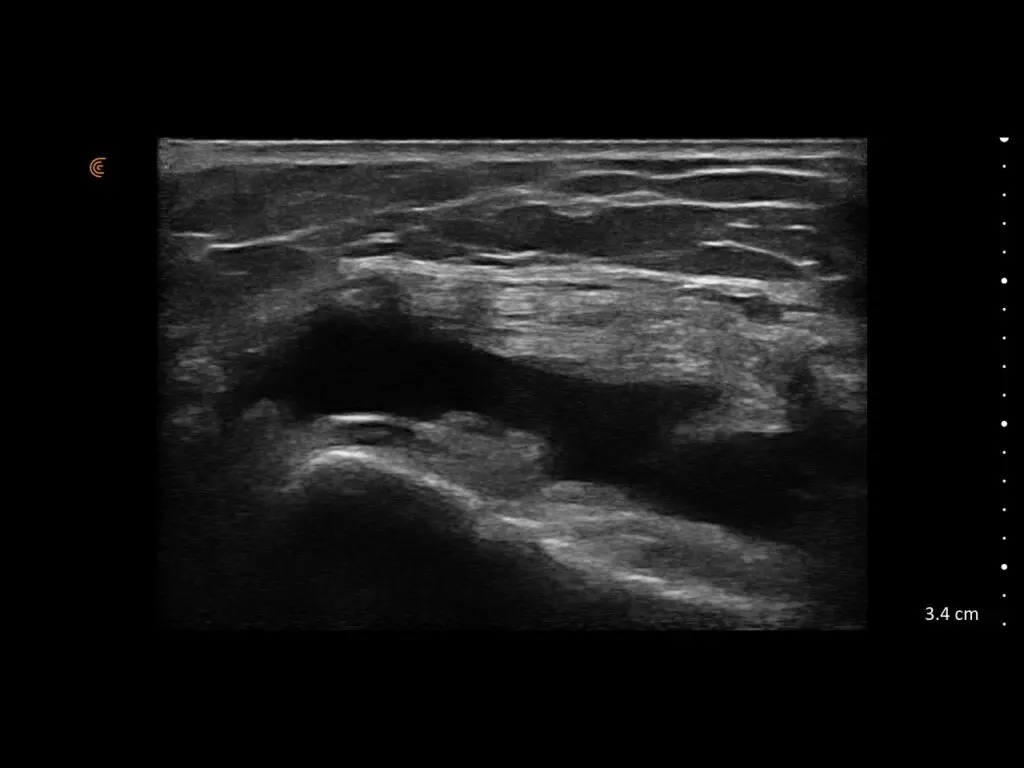

ProbeFix Dynamic is a new device that enables high-quality ultrasound measurements during dynamic exercise by keeping an ultrasound probe in place, allowing for muscle monitoring during intense movement and creating new research possibilities in muscle imaging.